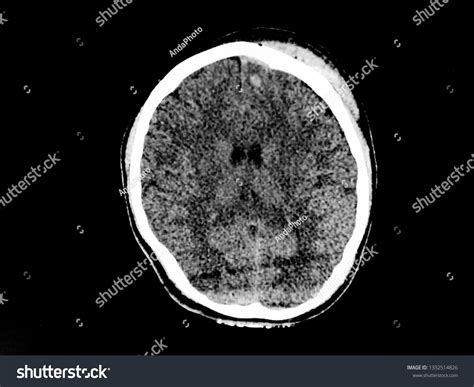

• Subacute Subdural Hemorrhage: Occurs between 3 to 20 days after the injury and may appear isodense or hypodense on CT images.

• Chronic Subdural Hemorrhage: Occurs more than 20 days after the injury and appears hypodense on CT images.

Case Study 2: A 70-year-old patient with a history of falls presented with confusion and weakness on one side of the body. A CT scan showed a hypodense collection consistent with a chronic subdural hemorrhage. The patient was managed conservatively with close monitoring and supportive care, and follow-up CT scans showed gradual resolution of the hemorrhage.